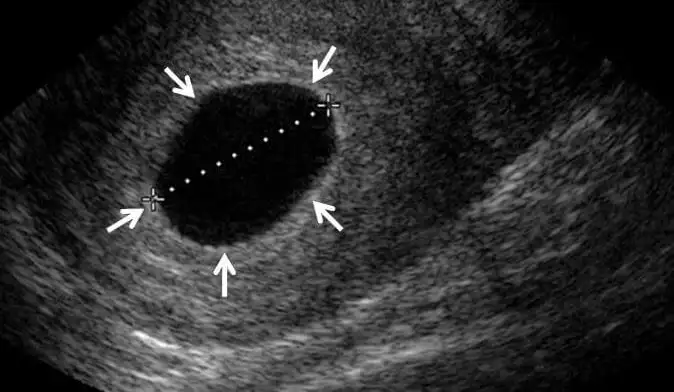

Bende hsg çektireceğim hsg den kaç gün sonra ilişki önerdi doktor acaba size bana flim çekileceğim güne kadar ilişki olmasın dediAdetim gecikince test yaptım öyle öğrendim ama hsg den sonra hep kasik ağrım vardı enfeksiyon kaptım diye düşündüm ama hamileymisim o yüzden agriyormus

Bugün anestezili hsg çektirdim 3 gün ilişki yasak dedi bir haftalık antibiyotik verdi. Hsg den önce de ilişki yasağı vermedi.Bende hsg çektireceğim hsg den kaç gün sonra ilişki önerdi doktor acaba size bana flim çekileceğim güne kadar ilişki olmasın dedi

Merhaba, bu ay hsg çektirdim ve adetim 3 gün gecikti. Dün yani gecikmenin 2. günü test yaptım negatif çıktı. Siz hamile olduğunuzu kaç gün sonra öğrendiniz? Her sabah uyanıp test yapacak gibi bir heyecan yaşıyorumEvett aynı ay hamile kaldım hsg çeken doktor bu şekilde hamile kalma ihtimalin sıfır demişti ama oldu Allah ol deyince oluyor umarım sizde hemen hamile kalırsınız:)

İnşallah hamilesindie bende 25 Nisan'da rahim filmi çektim benim de kasıklarımda sancı oluyor benim agrıyor aynen şiddetli değil ama insan umutlanıyor inşallah allah isteyen herkese nasip etsinİki hafta önce rahim filmi çekildim ve şu an kasıklarımda iki üç günden buyana ağrılar hissediyorum bacaklarıma ve belime vuran.( Şiddetli değil sızı gibi )Hamile kalabileceğim 11. Günümdeyim. Erken gebelik belirtisi olabilir mi?

Bnde gün hsg cekıldım baklm hayırlısı merakla umutla bekliyorum inşaallah bu ay kalırım